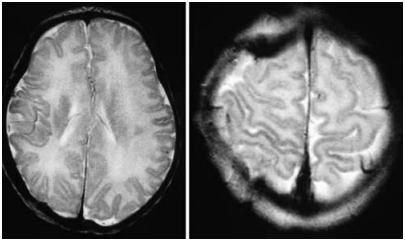

术后第3天,Alan从左半身开始出现偏侧癫痫;这些对静脉注射苯巴比妥有反应。给予地塞米松2天疗程。术后第5天,Alan顺利出院转至普通小儿神经外科,临床情况良好。术后MR影像学检查显示右侧血肿清除,左侧血块吸收(图3)。

图3:术后1个月复查MR检查,提示半球硬膜下出血、额叶挫伤治疗后的正常变化。